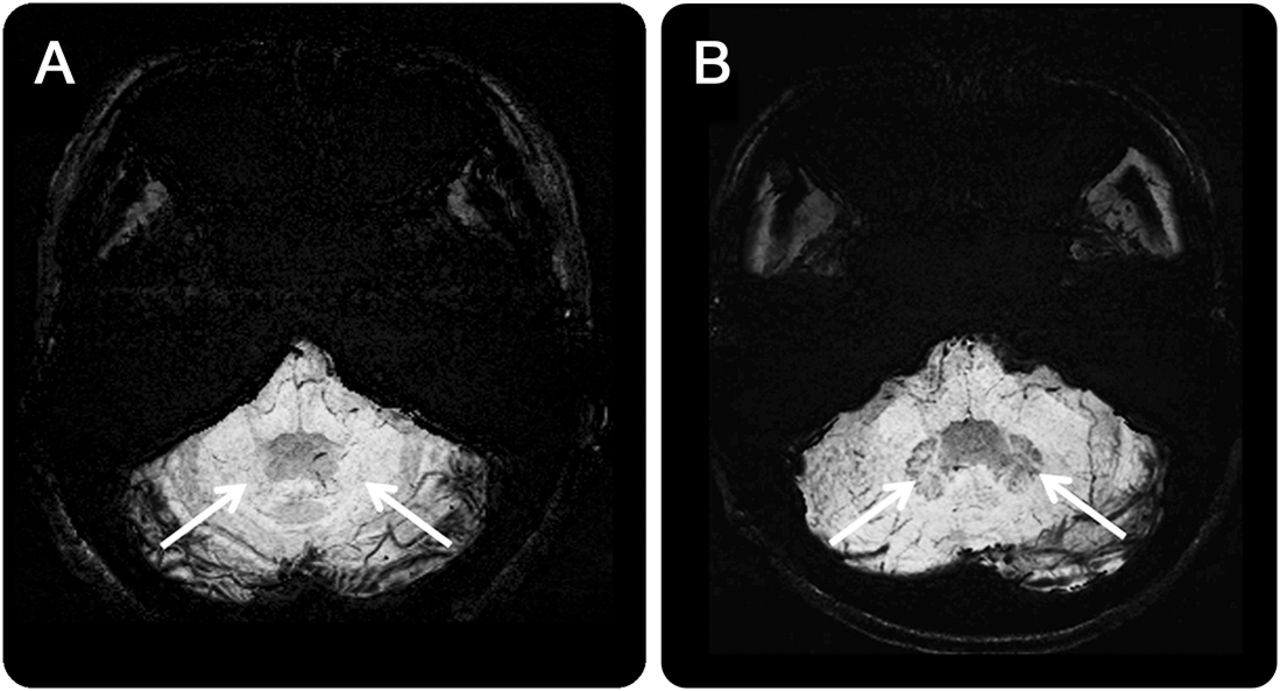

(一)t1加权磁共振成像显示小脑萎缩(箭头所指)。(B) Susceptibility-weighted图像(瑞士)显示点状的信号空间散射在正常大脑(箭头),表明microbleeds含铁血黄素沉积,有相关的扩张血管ataxia-telangiectasia患者中。